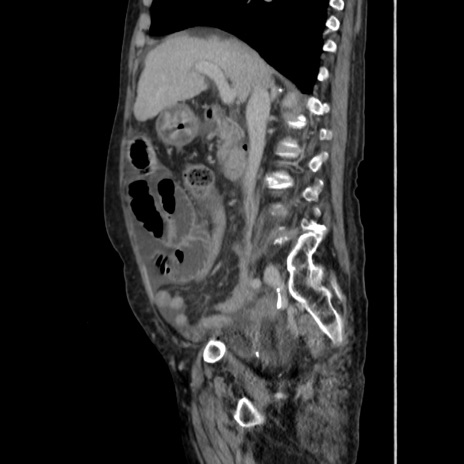

症例31(矢状断像)

【症例】80歳代 女性

【主訴】腹部膨満感

【現病歴】他院にて肝硬変にてフォロー中。1週間前から便秘、腹部膨満感、臍部腫瘤あり受診となる。

【既往歴】肝硬変

【身体所見】腹部膨隆あり、皮膚変化なし、疼痛なし。

【データ】WBC 4600、CRP 0.25